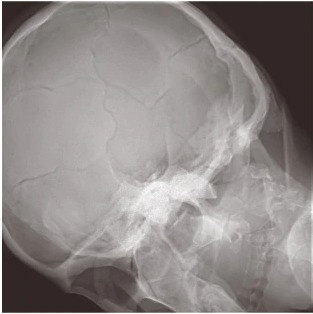

SyncTraX(SMART version)で撮影した2方向の画像(DR画像)と,治療計画CT画像から作成したDRR画像とを比較することで,治療計画位置からのズレ量を算出し,治療装置に送信できます。ガントリやカウチ回転時も2方向から迅速に撮影が行えますので,スピーディーな位置決めが可能です。また,各治療ポジションにて位置決めが行えます。

大視野・高精細画像が精度の高い位置決めを支援

大視野FPDの搭載により,広いダイナミックレンジが画像の黒潰れやハレーションを低減するとともに歪のない画像を提供しますので,精度の高い位置決めを支援します。